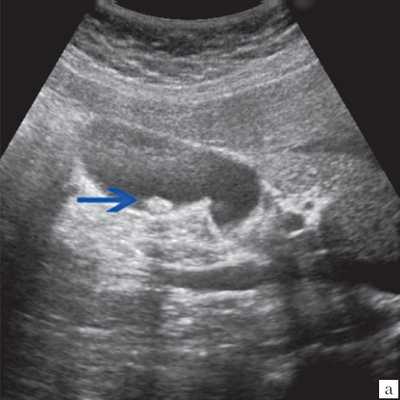

- Ультразвуковое исследование (УЗИ). Основным признаком МЖ при УЗИ является расширение внутрипеченочных желчных протоков (рис. 1). УЗИ позволяет не только выявить билиарную гипертензию, но и установить уровень блока.

При высоком билиарном блоке (обтурация на уровне ворот печени) при УЗИ визуализируются расширенные внутрипеченочные протоки при нормальном диаметре ОЖП (до 6 мм), желчный пузырь чаще нормальных размеров или уменьшен, возможно выявление в воротах печени объемного образования.

Рис. 1. Ультразвуковая картина билиарной гипертензии при механической желтухе.

а) Расширенные внутрипеченочные протоки.